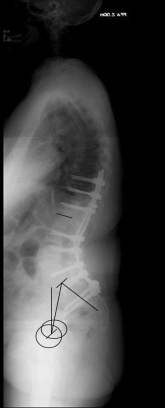

Adulte Def. IAdulte Def. II

X-ray image before and after surgery. The patient underwent spinal surgery at another hospital and increasingly developed other complaints. The X-ray showed a complete loss of the hollow back and a resulting change in balance. A so-called lordosis operation led to a restoration of a normal hollow back and thus a normal spinal balance and finally to regressive complaints.